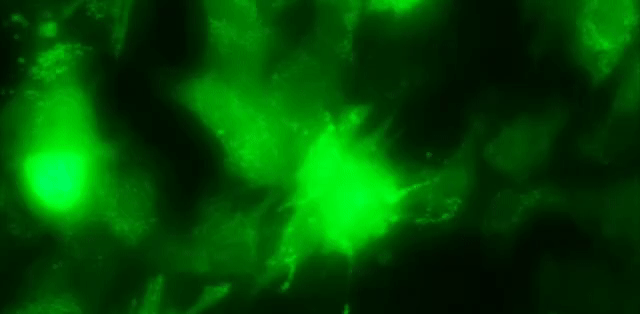

Direct cardiac reprogramming approach uses specific genes to directly convert the fibroblasts into cardiac myocytes. At the Center for Cardiac Engineering & Regenerative Therapeutics in the Department of Surgery, we are developing innovative gene therapies based on direct cardiac reprogramming, a cutting-edge approach that transforms existing cells into heart cells. Our preclinical studies have shown promising results, including improved heart function and tissue regeneration following gene delivery. To ensure safety and efficiency, we are exploring multiple delivery methods-such as viral vectors and non-viral techniques-to introduce therapeutic genes into the heart. In addition, our research focuses on identifying: